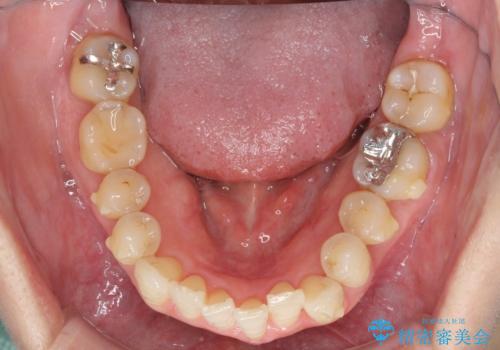

- 下顎の八重歯と、上下のクロスバイトを気にして来院された患者様です。

インビザラインを用い、下顎全体の後方移動、IPR(歯と歯の間を削る)と歯列全体を拡大させることで、歯並びを整えていくこととしました。